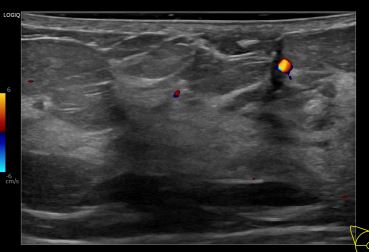

상기환자는 우측유방 만져지는 멍우리있어  내원하신 40대중반 여성분으로 의심스러운 우측혹 조직검사 시행해 유방암 진단되었습니다.